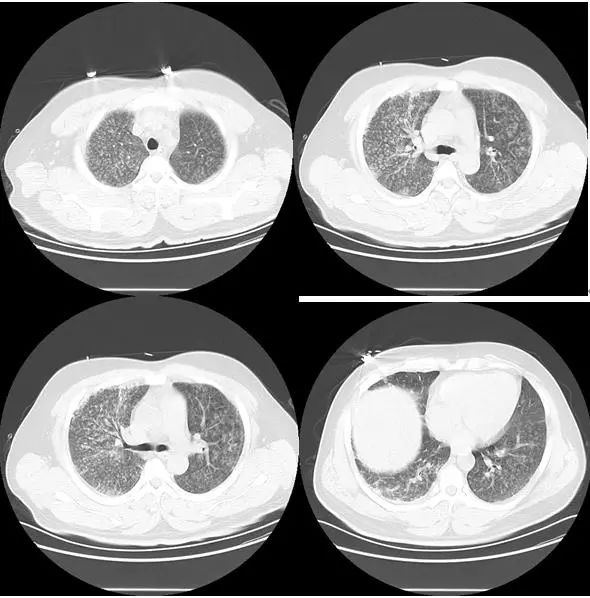

辅助检查:肺部CT:两肺感染及感染后改变。血沉75(0~20 )mm/h↑;乳酸脱氢酶 308U/L↑(88~240 U/L);铁蛋白 477.2μg/L↑;抗核抗体:抗双链DNA(抗dsDNA) <100IU/ml;抗核抗体 1:320↑;支气管镜:右侧支气管变形,支气管炎症。三大常规、肺炎支原体、衣原体抗体、PPD试验、肿瘤系列、肝肾功能、甲状腺功能、降钙素原、尿培养、血培养、BALF培养及抗酸杆菌均正常。

图7 肺部CT

图8 肺部CT

图9 肺部CT

治疗过程:患者诊断为“肺炎”,予“头孢西丁针联合左氧氟沙星针”抗感染治疗,仍持续发热,体温波动36.5-38.2℃,不规则热热型。改美罗培南针治疗,热仍未退并且出现了呼吸费力,指测氧饱和度95%下降至90%,肌炎谱回报:MDA5抗体阳性。予甲强龙针、他克莫司、丙种球蛋白及SMZ预防耶氏肺孢子菌肺部感染治疗,预后不良。

该病例提示,1.皮肌炎特别是MDA5抗体阳性皮肌炎可无皮疹;2.血清铁蛋白、乳酸脱氢酶对于无肌病性皮肌炎相关间质性肺疾病有诊断及死亡风险预测价值[5];3.临床医师需熟悉影像学知识;4.抗核抗体对于结缔组织疾病所致发热有诊断价值。